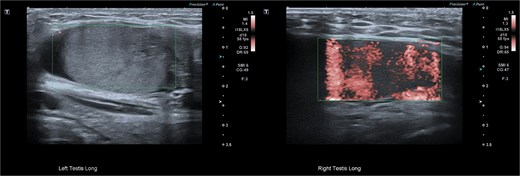

Closure was performed in layers, and local anaesthetic was infiltrated. The procedure was well tolerated. Follow-up at four weeks showed preserved testicular position with normal Doppler inflow and normal echotexture (Fig. 7).

Follow-up ultrasonographic image at 4 weeks post-operatively, demonstrating the left testis within the scrotum, with restored homogeneous echotexture and normal intratesticular vascularity on colour Doppler.